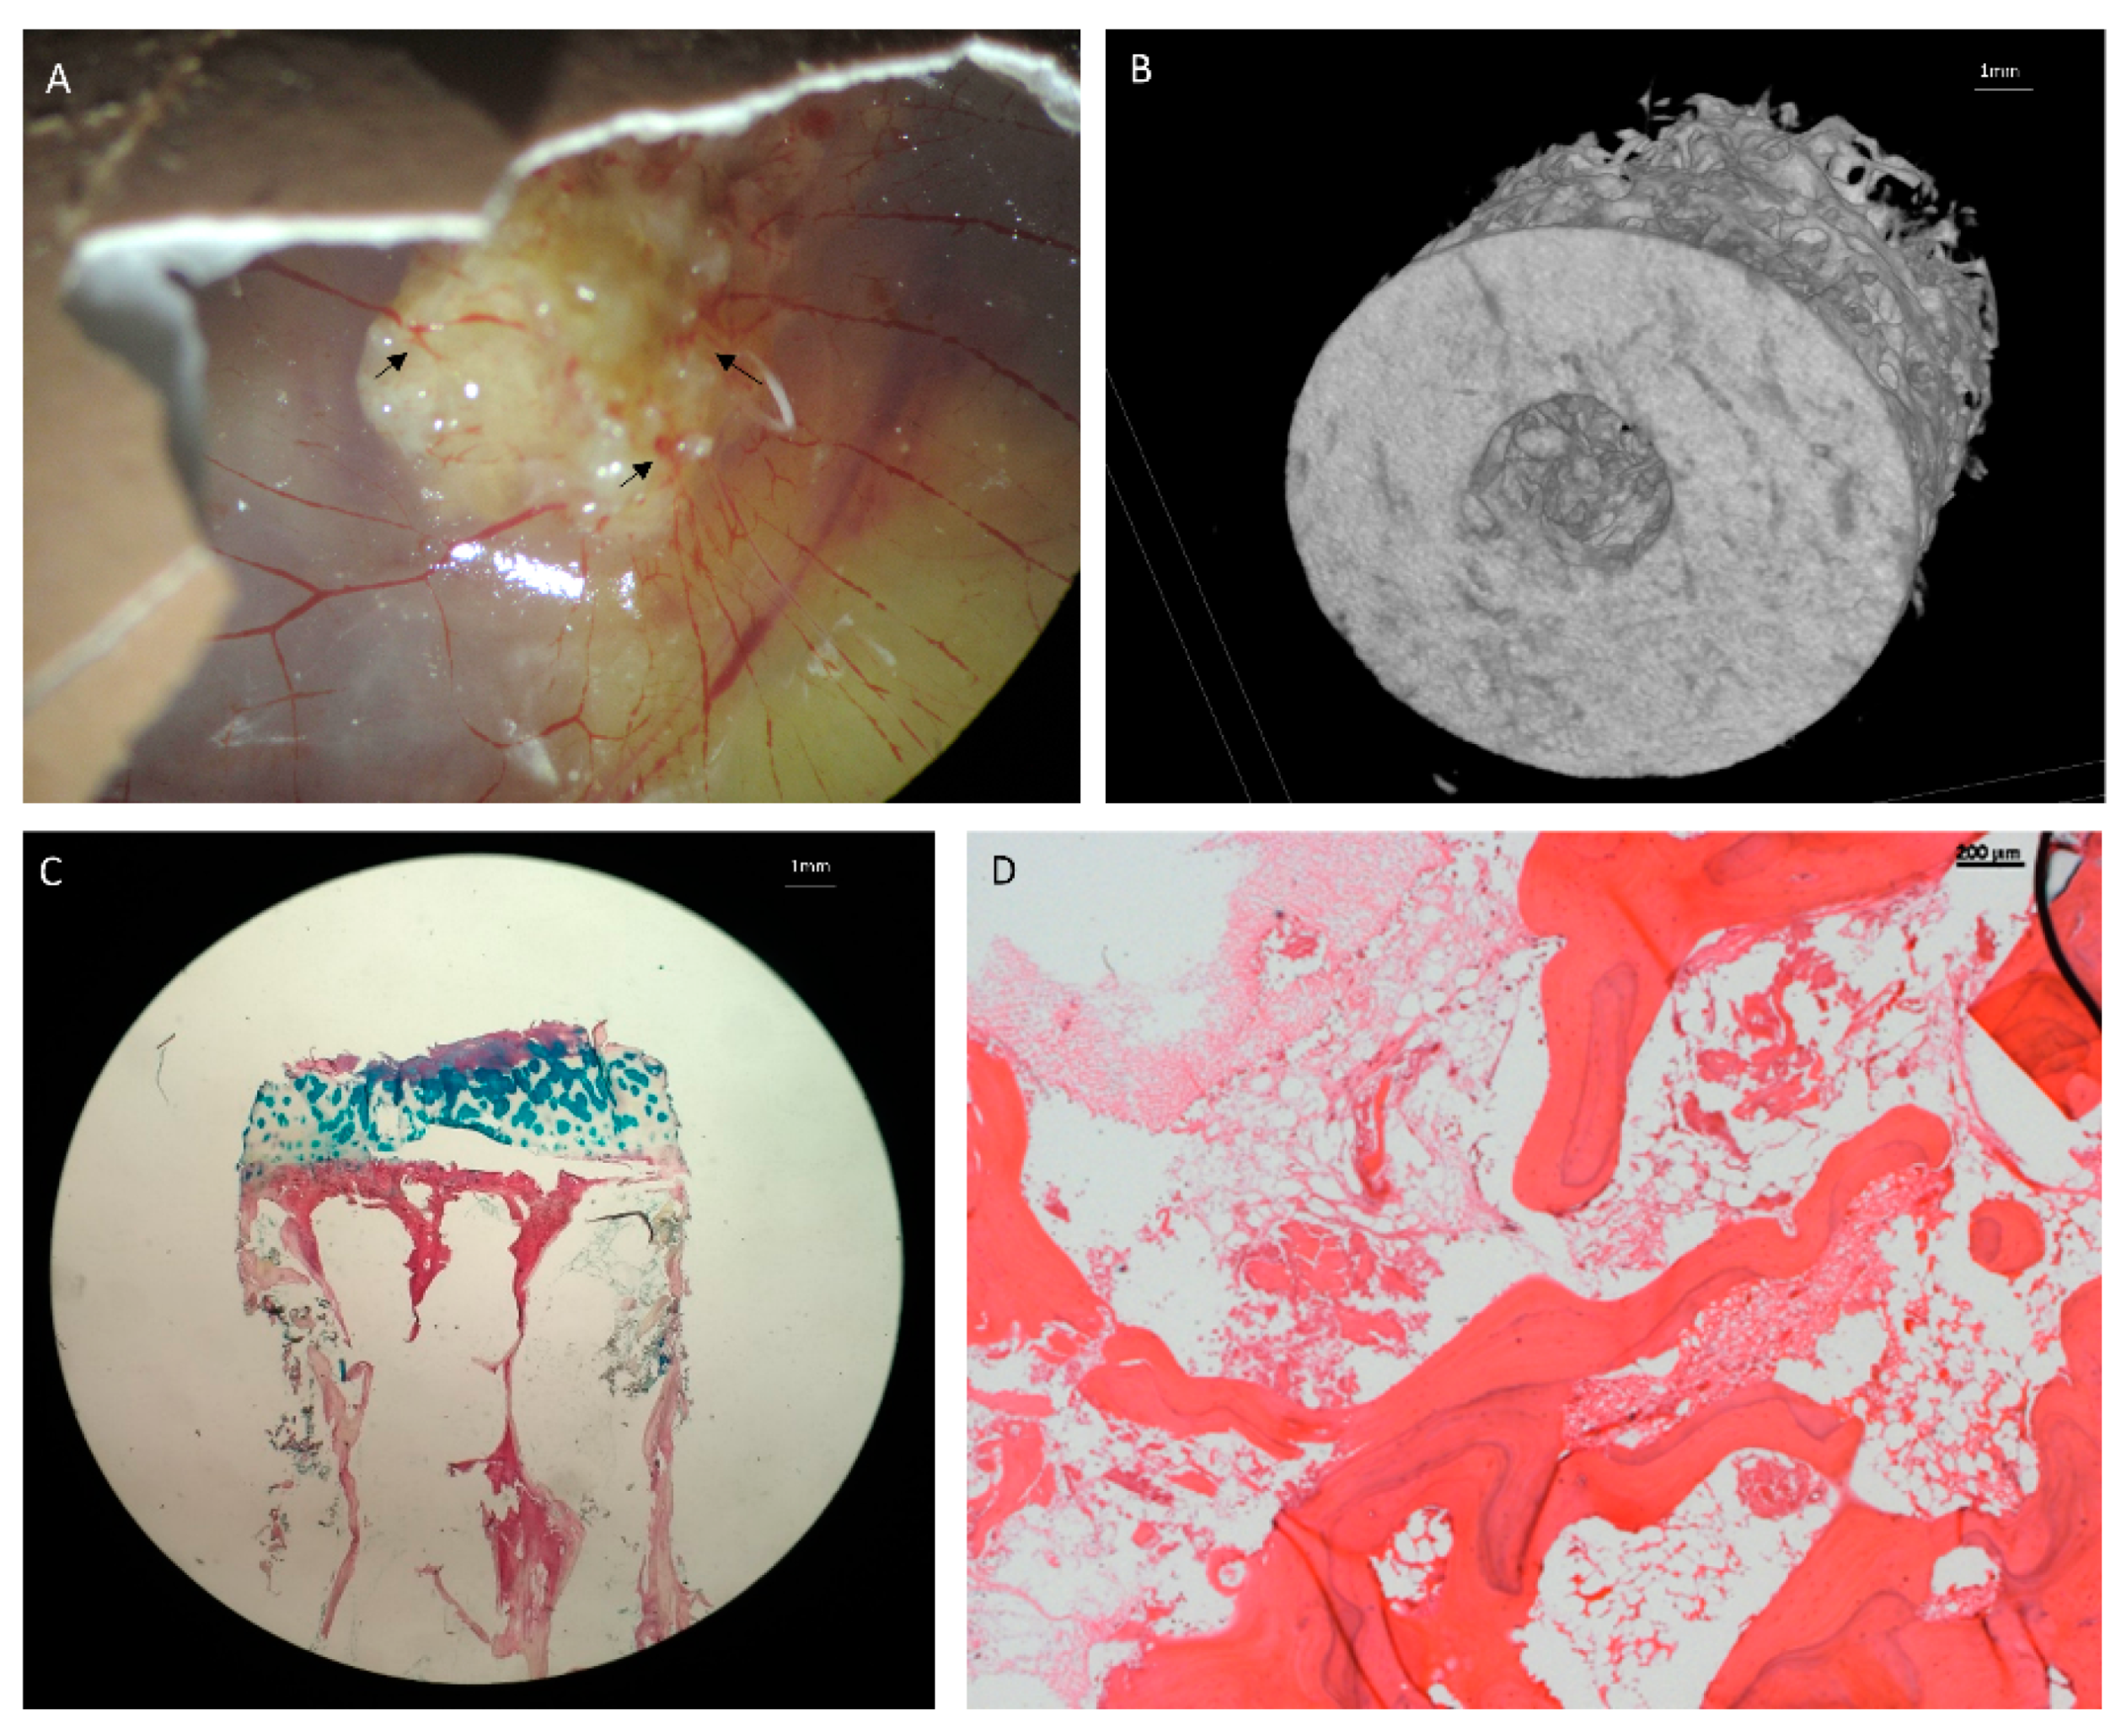

- Balke, M.; Neumann, A.; Kersting, C.; Agelopoulos, K.; Gebert, C.; Gosheger, G.; Buerger, H.; Hagedorn, M. Morphologic characterization of osteosarcoma growth on the chick chorioallantoic membrane. BMC Res. Notes 2010, 3, 58. [Google Scholar] [CrossRef]

- Manjunathan, R.; Ragunathan, M. Chicken chorioallantoic membrane as a reliable model to evaluate osteosarcoma-an experimental approach using SaOS2 cell line. Boil. Proced. Online 2015, 17, 10. [Google Scholar] [CrossRef][Green Version]

- Moreno-Jimenez, I.; Lanham, S.A.; Kanczler, J.M.; Hulsart-Billstrom, G.; Evans, N.D.; Oreffo, R.O.C. Remodelling of human bone on the chorioallantoic membrane of the chicken egg:De novobone formation and resorption. J. Tissue Eng. Regen. Med. 2018, 12, 1877–1890. [Google Scholar] [CrossRef] [PubMed]